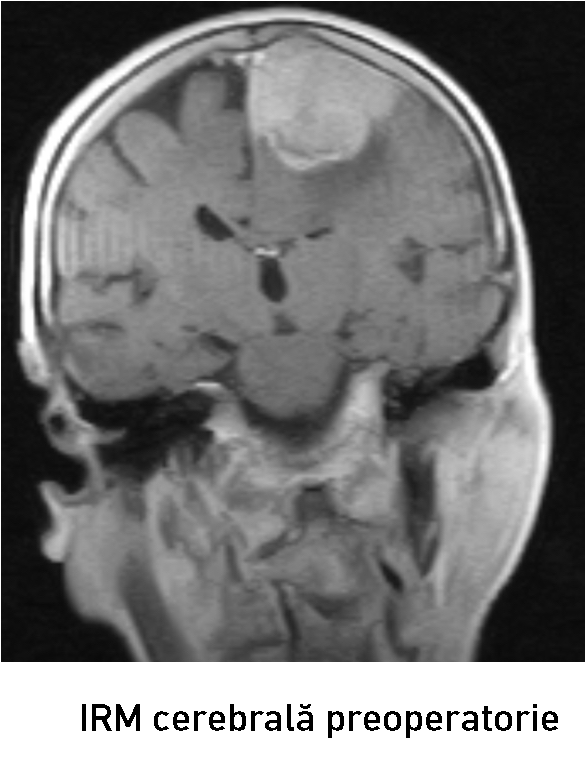

Examenul neuroimagistic prin IRM a stabilit prezența unei formațiuni tumorale intracraniene extraaxiale pe stânga (6

6 x 37 x 45 mm)la nivelul parasagital (1/3 medie a SSS) ce comprima regiunea precentrală și postcentrală stângă (fig. 1-2). Formațiunea de volum era atașată de sinusul sagital superior, de coasa creierului și capta intens substanța de contrast – suspect pentru un meningiom parasagital voluminos. Luând în considerație volumul leziunii tumorale, se impunea realizarea tratamentului neurochirurgical.